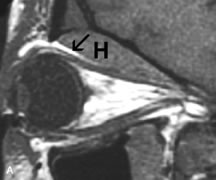

MRI is particularly helpful in the detection and characterization of subperiosteal hematomas of the orbit (Fig. 19). They are most commonly seen in the subperiosteal space of the superior orbit as well-defined masses following a traumatic injury. The signal intensity varies depending on the acute, subacute, or chronic nature of the hematoma, based on the stage of blood degradation. Fresh hemorrhages are hypointense on T1-weighted images and hyperintense on T2 images. Hematomas that are 1 to 7 days old are hypointense on both T1- and T2-weighted images. T1-weighted images of hematomas more than a week old are hyperintense due to the oxidation of deoxyhemoglobin to methemoglobin, whereas the T2 images remain hypointense.63

Fig. 19. A. T1- and (B) T2-weighted MR scans demonstrate a large acute subperiosteal hematoma (H) that lies between the cortical bone of the orbital roof and the inferiorly displaced periorthira (double arrow). The extracopal fat (arrow) and levator muscle are displaced inferiorly.